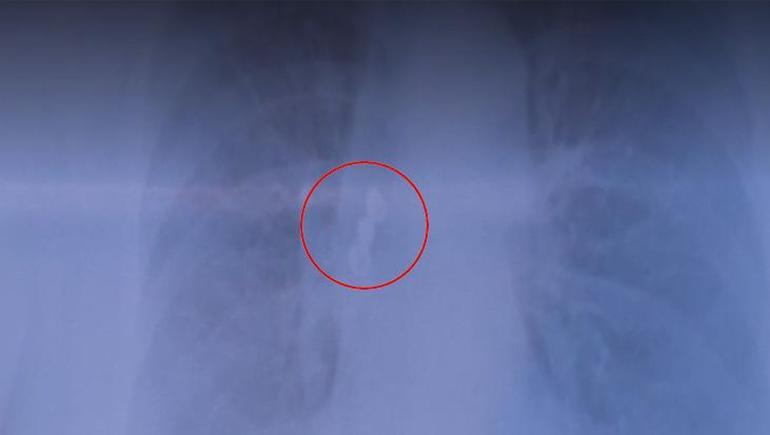

Kadın hastanın üst arka tarafta bulunan üçlü kaplama dişi akciğerine kaçtı. Sabah uyandığında dişlerinin yerinde olmadığını gören hasta acilen hastaneye başvurdu. Çekilen röntgen filminde dişlerin akciğerde olduğu görüldü. Hasta şanslıydı, çünkü soluk borusu tamamen tıkanabilirdi. Akciğerdeki diş bronkoskopi yöntemiyle çıkarıldı.

Göğüs Hastalıkları Uzmanı Prof. Dr. Levent Alpay, akciğer filminde üç dişten oluşan kaplama köprüsünün aspire edildiğini fark ettiklerini ve hastayı hemen yatırdıklarını söyledi. Sabah uyandığında dişlerinin yerinde olmadığını gören hastanın, dişleri yutmuş olabileceğini düşündüğünü belirten Alpay, bu tür durumlarda genellikle mideye kaçma ihtimalinin daha yüksek olduğunu vurguladı.

"Çekilen akciğer filminde kaplama dişin üç dişten oluşan kısmının aspire edildiğini görerek hastamızı hemen yatırdık. Sabah uyandığında dişlerinin ağzında olmadığını gören hasta, “Acaba yuttum mu?” diye düşündü. Genelde bu tür durumlarda yutma söz konusu olur.